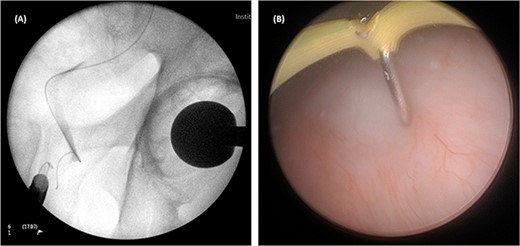

On Day 5 post-operatively, bilateral nephrostograms revealed bilateral ureteric occlusion at the level of the VUJ with extravasation at the right side (Fig. 1). An attempted antegrade ureteric stent insertion failed. The patient was thereafter booked electively for a rigid cystoscopy and bilateral ureteric stenting 3 weeks following the original operation.

On both cases, under general or regional anaesthesia, a cystoscopy was performed and the interureteric bar was identified. A hybrid ‘sensor’ or ‘Terumo’ hydrophilic guidewire was advanced concurrently using the access from the existing nephrostomy tube with fluoroscopic assistance down to the level of the ureteric cul-de-sac. A combined visual- and x-ray-guided approach verified the exact location of the course of the intramural ureter, in correlation to the resectoscope and a Collins knife was used to incise the bladder mucosa (Fig. 2) above the level of the guidewire, on the virtual course of the intramural ureter exposing the intramural ureter. In all three attempts, the incision of bladder mucosa above the antegrade ureteric guidewire ended up with a successful identification of the guidewire, allowing access to the ureteric cul-de-sac. Stent graspers were used to snare the guidewire into the bladder (Fig. 3). With safety wire in place, management of the neo-orifice could then be performed.

A combined visual- and x-ray-guided approach verified the exact location of the course of the intravesical intramural right ureter, in correlation to the resectoscope. (A) X-ray, (B) cystoscopic view.